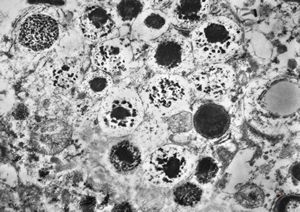

M,48y. | cornea - Fabry disesase